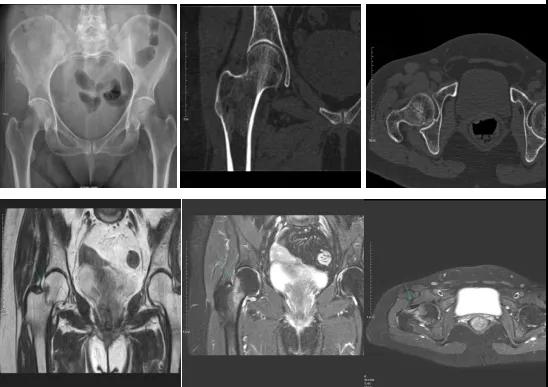

2.CT或MRI檢查。CT是斷面成像,不會(huì)出現(xiàn)重疊而導(dǎo)致漏診,同時(shí)CT還可以進(jìn)行多平面的重建,除了發(fā)現(xiàn)X線無(wú)法發(fā)現(xiàn)的骨折外,還可以三維直觀的顯示骨折的程度,對(duì)臨床治療有指導(dǎo)意義。CT無(wú)法發(fā)現(xiàn)骨裂、不全骨折或者骨挫傷,對(duì)軟組織的損傷診斷也有局限性,MRI就可以發(fā)現(xiàn)這些損傷。

DR示:右側(cè)股骨頸未見(jiàn)明顯骨折征象。CT右側(cè)股骨頸骨質(zhì)密度不均?;颊唧w征明顯,為明確診斷,行MRI檢查。MRI示:右側(cè)股骨頸T1WI呈低信號(hào),脂肪抑制序列呈高信號(hào);提示右側(cè)股骨頸隱匿性骨折。